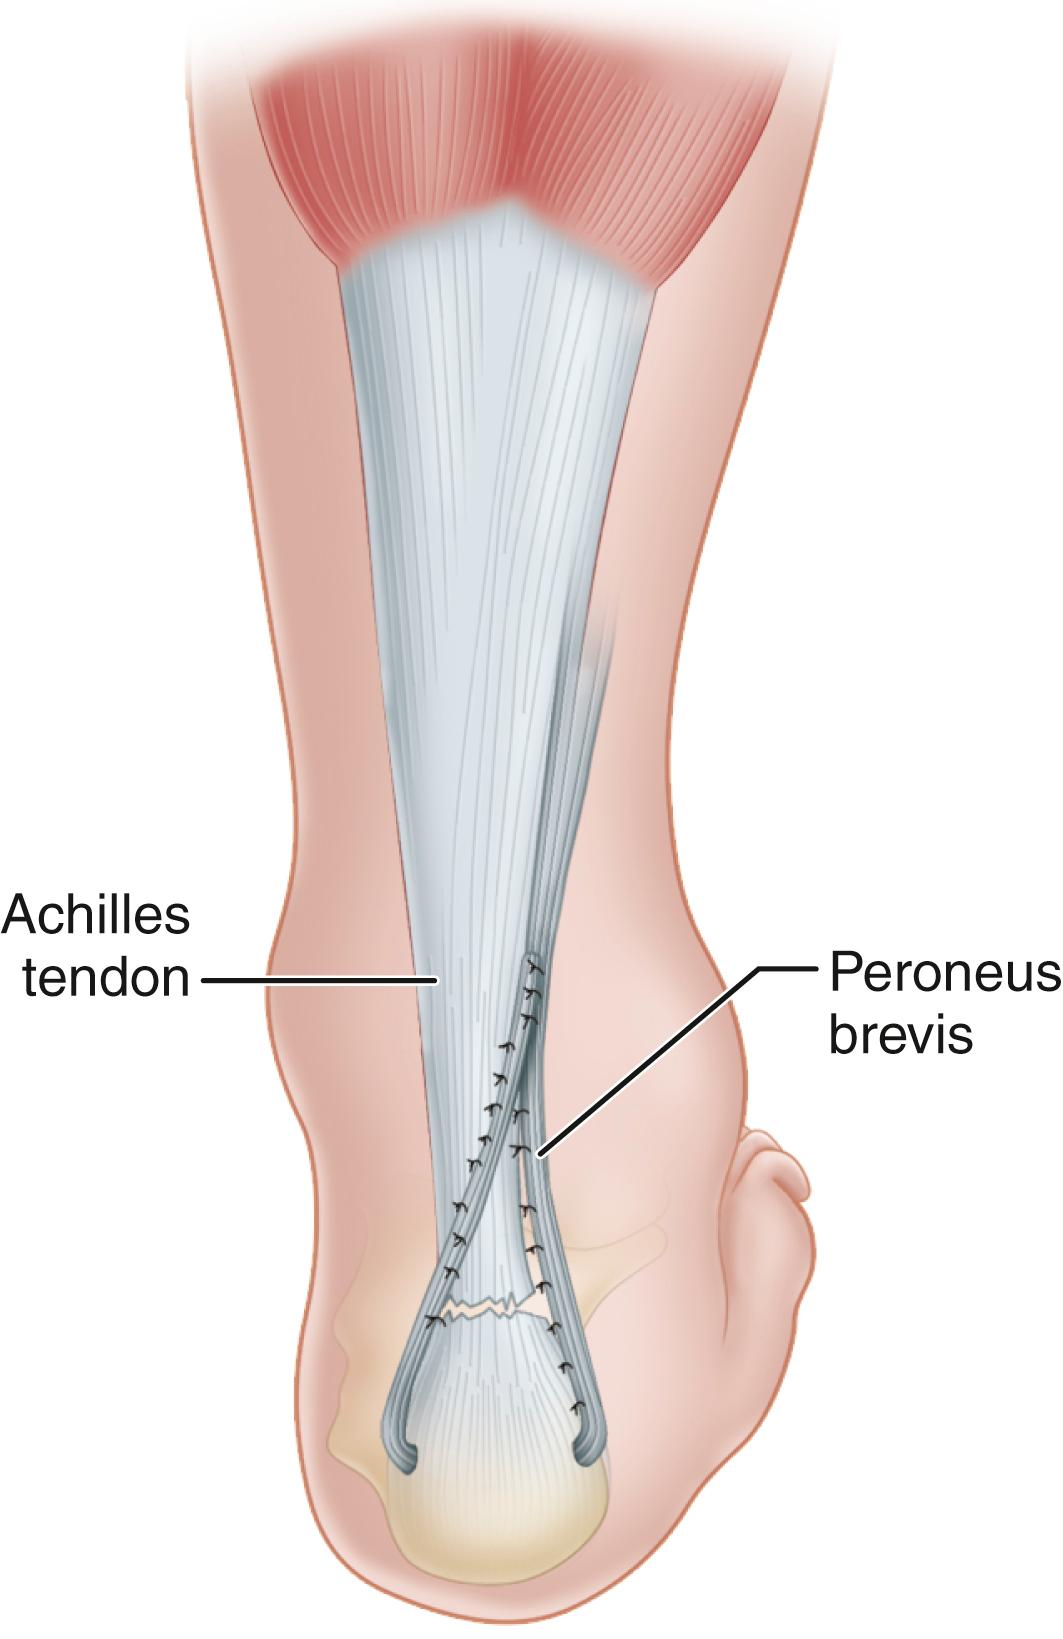

• Detach the peroneus brevis tendon from its insertion through a small incision at the base of the fifth metatarsal.

• Excise the aponeurotic septum, separating the lateral and posterior compartments, and deliver the freed peroneus brevis into the first incision.

• Dissect the tuberosity of the calcaneus and drill a hole large enough for passage of the tendon through the transverse diameter of the bone.

• Pass the peroneus brevis tendon through this hole and back proximally beside the Achilles tendon, reinforcing the site of rupture, and suture it to the peroneus brevis itself, producing a dynamic loop ( Fig. 48.19 ).

FIGURE 48.19, Dynamic loop suture of peroneus brevis to itself when end-to-end suture is not possible. SEE TECHNIQUE 48.11 .

Turco and Spinella described a modification in which the peroneus brevis is passed through a midcoronal slit in the distal stump of the Achilles tendon. The graft is sutured medially and laterally to the stump and proximally to the tendon with multiple interrupted sutures to prevent splitting of the distal tendon stump ( Fig. 48.20 ). This modification can be beneficial if a long distal stump is present.

FIGURE 48.20, Turco and Spinella modification. Peroneus brevis is passed through midcoronal slit in distal stump of Achilles tendon and sutured to stump and to tendon. SEE TECHNIQUE 48.11 .